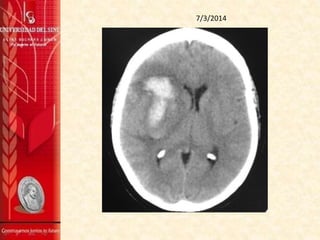

TAC DE CRÁNEO SIN CONTRASTE 7/3/2014

Se observa una imágen hiperdensa que compromete la

región ganglio-basal derecha, de contornos difuminados, de

aproximadamente 40 mm por 19 mm, en el plano axial con

aspecto de hematoma intraparenquimatoso, sus contornos

hacen pensar en una evolución hacia la cronicidad.

Hay discreto efecto de masa dado por el edema alrededor de

la lesión que está desviando la línea media unos 7 mm a la

izquierda.

No se aprecian masas extra axiales.

La fosa posterior es normal.

IMPRESIÓN:

1. Hematoma intraparenquimatoso en la la región ganglio-

basal derecha.

7 MARZO 2014

Paciente femenina de 42 años de edad con antecedentes

de migraña, actualmente en estudio de etiología de

hemorragia intraparenquimatosa evidenciada en TAC

cerebral sin contraste inicial, con reporte de

panangiografia normal, aun persiste hemiparesia

izquierda (fuerza muscular ahora 3/5). En la actualidad

vista con Medicina interna y Neurocirugia, en manejo

médico espectante , estricto seguimiento neurològico.

Se maneja con: nimodipino de 30 mg vo al día,

acetaminofen 500 mg via oral cada 6 horas, atorvastatina

40 mg dia via oral, furosemida 20mg IV día.